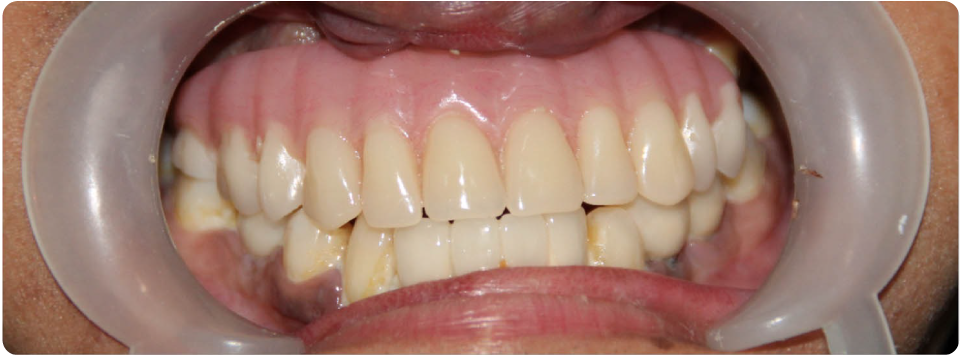

Complex Implant Rehabilitation

Complex dental implant rehabilitation is a highly effective solution for patients with extensive dental issues.

Such as severe bone loss, multiple missing teeth, cases involving tumor resection and reconstruction with vasculised bone grafts, gun shot injuries, with cleft lip and palate, jaw necrosis, post cancer oral rehabilitation.